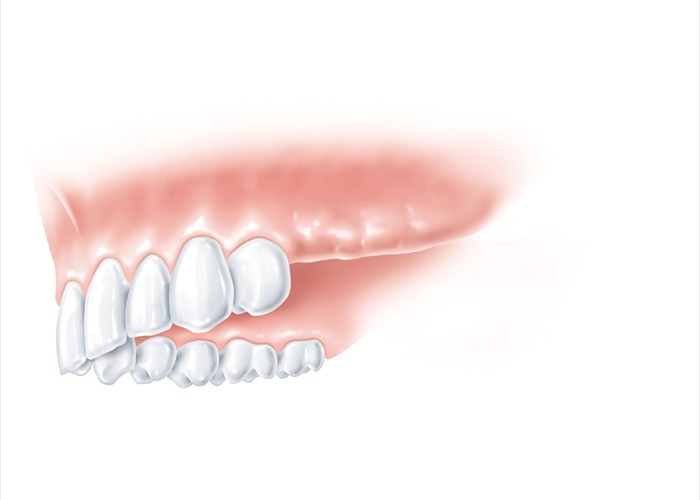

Die drei hinteren Zähne fehlen. Hier muss in der Regel ein herausnehmbarer Zahnersatz angefertigt werden.

Die drei hinteren Zähne fehlen. Hier muss in der Regel ein herausnehmbarer Zahnersatz angefertigt werden.